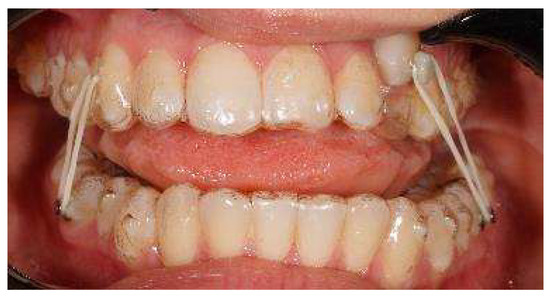

Final clinical records show good aesthetics and the functional recovery of upper canines in the arch. A Class I canine relationship was achieved, and overbite and overjet were normalized. The coordination of the maxillary and mandibular midline was carried out (Figure 9).

Figure 9.

Post treatment extraoral and intraoral pictures.